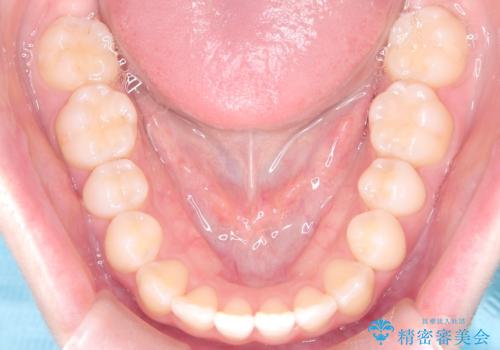

- 右上の前歯(2番)が下の歯より内側に入っている反対咬合を主訴にご来院されました。精密な検査の結果、この反対咬合を解消するためには、右上の歯列に前歯を出すためのスペースを確保する必要があると判明しました。患者様のご希望に合わせ、透明で目立たないインビザライン(マウスピース矯正)による治療計画を立案。奥歯全体を奥へ動かす遠心移動でスペースを作り、反対咬合を解消することを目指します。

今回の矯正治療では、透明なマウスピース型の装置インビザラインを使用しました。治療は、緻密なデジタル計画に基づき、奥歯から順に歯列全体を後方へ移動させる遠心移動を実施し、前歯を前に出すためのスペースを確保しました。このスペースを利用して、内側に入り込んでいた右上2番をスムーズに前方に誘導し、正常な咬み合わせへと改善。目立たないインビザラインで、機能的な咬み合わせと美しい前歯の並びを獲得していただけました。